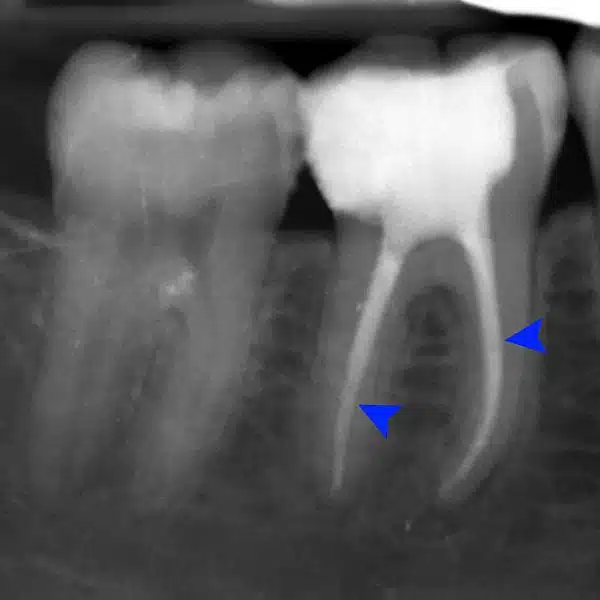

To get a clearer view of what endodontic treatments entail, it’s crucial that you get an overview of the tooth. On the outside of the tooth, you have the white enamel along with a hard layer called the dentin. Beneath these layers you have the pulp, which is the soft tissue that also contains the blood vessels, nerves, and other connective tissue.

The pulp extends from the crown of the tooth right to the very tips of the root. At that point, it connects to the various tissues around the root. The pulp is crucial during the growth and development of the tooth as it helps to nourish the tooth. But once the tooth is fully developed it can survive without the pulp. The tooth can be nourished without the pulp because of the tissues around it.

When the pulp becomes infected or inflamed, endodontic treatment may be needed. This infection may be due to tooth decay, a chip in the tooth that lets bacteria in, or damage due to repeated dental procedures on the tooth. In some cases, a hard blow to the tooth can damage the pulp even when there are no visible chips in the tooth.